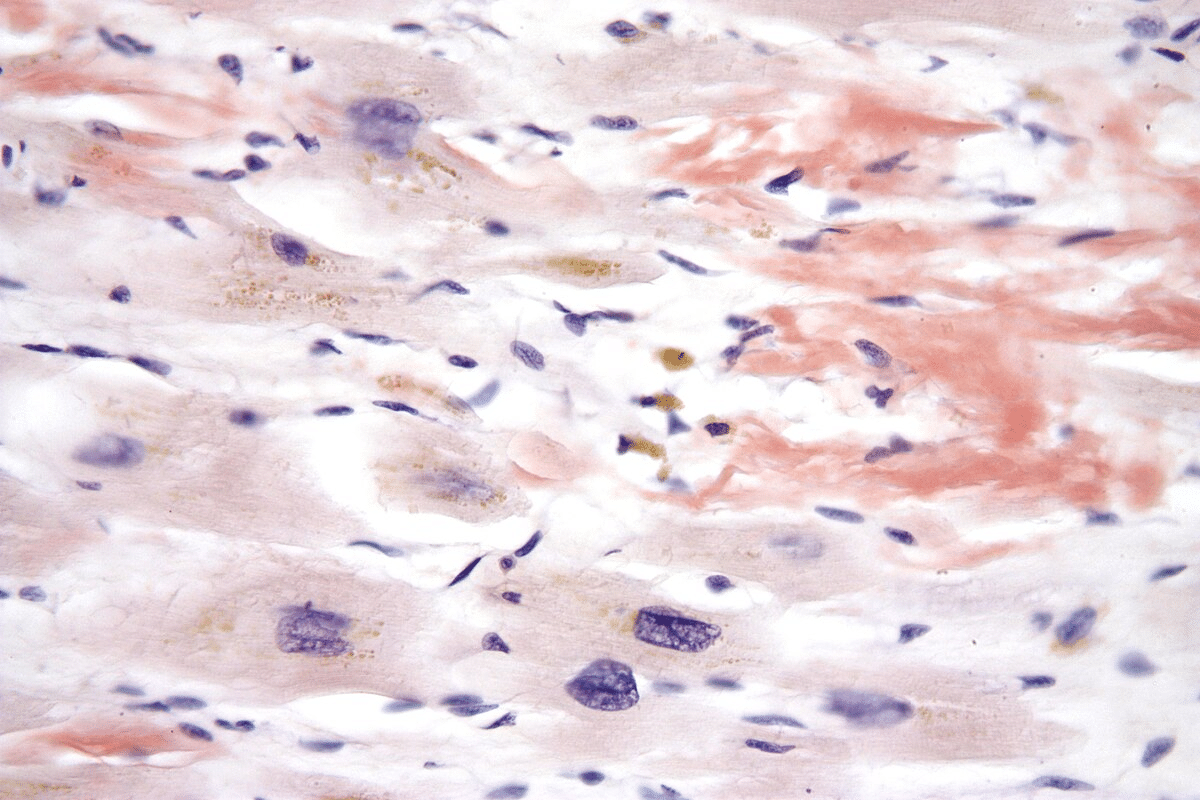

» Light chains kappa (97) 사진

Light chains kappa (97) 사진